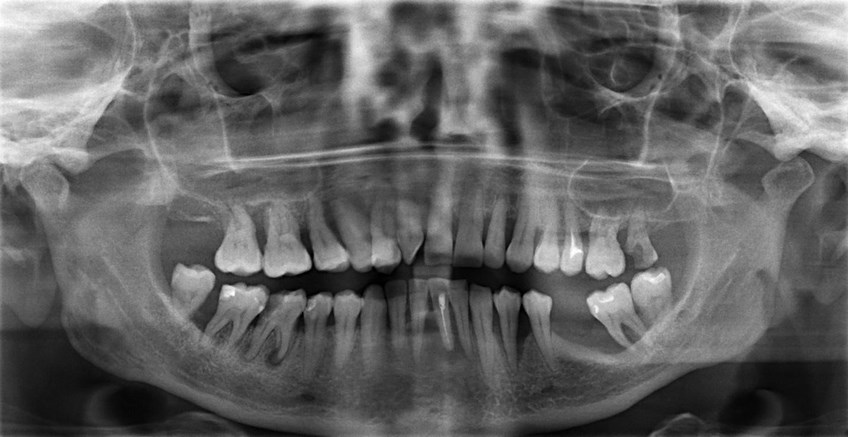

Если в прошлом проводилось протезирование, то при подготовке к лечению нужно обратить пристальное внимание на коронки. На каких зубах они установлены? В каком состоянии корни этих зубов? Не начали ли разрушаться коронки, места их соединения? На какие зубы будет наибольшее воздействие, а какие будут перемещаться на 1–2 мм? Ответив на эти вопросы, доктор сможет сказать, можно ли носить элайнеры или брекеты

Иногда нужно сначала переделать коронку, а затем уже лечиться у ортодонта.

Коронки, в отличие от имплантов, перемещать можно (но осторожно)

Большое количество пломб.

Если у вас запломбированы 10 и более зубов, сами пломбы крупные (занимают больше 50% объема зуба), а в некоторых зубах были удалены нервы, это не значит, что исправлять прикус нельзя. Просто нужно более тщательно обследовать все пломбы и уточнить, не начали ли они разрушаться. Старые пломбы врач может порекомендовать заменить. Современные материалы для лечения позволяют сохранять даже «мертвые» зубы.